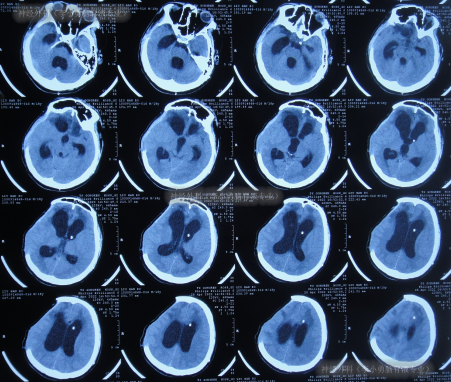

继续治疗1月期间出现数次呕吐,行胃肠镜检查未见异常(片子丢失),给予胃管及肠管置管,期间5次查头颅CT(图-5)均示脑室逐渐出现扩张,并加重。

图-5:5次查头颅CT

去骨瓣减压术后36天即2022年3月9日,复查头颅CT(图-6)示脑室扩张更严重了,脑膨出。

图-6:2022年3月9日头颅CT